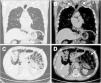

ResultadosLa incidencia de neumatosis intestinal postrasplante pulmonar en nuestro centro fue del 3,1% (17/546), desarrollándose entre 9 y 1270 días tras el trasplante (media, 198 días; mediana 68 días). La mayoría de los pacientes estaban asintomáticos o con síntomas leves, sin grandes alteraciones analíticas, y con un aspecto radiológico quístico y expansivo. Asoció neumoperitoneo en un 70% (12/17). Se optó por un tratamiento conservador en todos los casos. El tiempo medio hasta la resolución fue de 389 días.

ResultsThe incidence of pneumatosis intestinalis after lung transplantation in our center was 3.1% (17/546), developing between 9 and 1270 days after transplantation (mean, 198 days; median 68 days). Most of the patients were asymptomatic or with mild symptoms, without any major analytical alterations, and with a cystic and expansive radiological appearance. Pneumoperitoneum was associated in 70% of the patients (12/17). Conservative treatment was chosen in all cases. The mean time to resolution was 389 days.